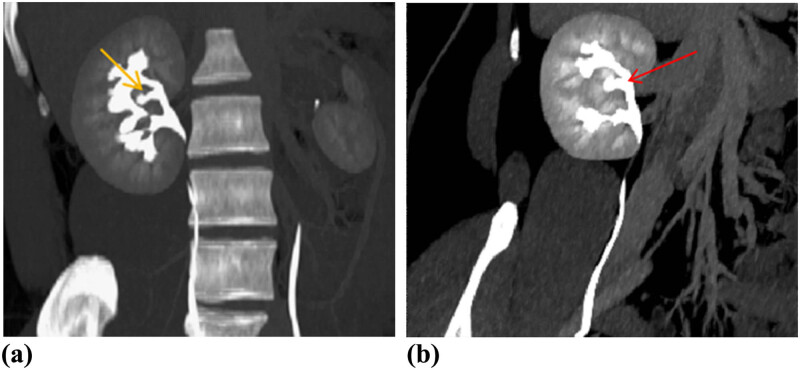

Figure 3.

Pyelographic phase coronary MIP (a) and CPR (b) images demonstrated that the little renal pelvis (yellow arrow) from renal shaped mass in the renal sinus drained into the calyces of the upper pole of right kidney (red arrow). MIP = maximum intensity projection; CPR = curved planar reconstruction.

CT urography (CTU) was performed to evaluate the renal lesion more accurately. Plain CT demonstrated an isodensity mass to normal renal parenchyma with unclear boundary in his right renal sinus without hydronephrosis (Figure 2a). The size of lesion was 14 × 5 × 3 mm. Renal contrast-enhanced CT (CECT) showed the intrarenal sinus mass that exhibited the enhancement mode similar to kidney: wheel-spoke shaped enhancement of renal cortex and no enhancement of renal medulla in corticomedullary phase, and homogeneous enhancement in parenchymal phase (Figure 2b and c). Pyelographic phase images demonstrated that a renal pelvis shaped structure from mass merged into the right major renal calyces (Figure 2d). Coronal maximum intensity projection (MIP) CT image in pyelographic phase directly revealed that the mass in renal sinus sent out a renal pelvis shaped structure and merged into the right upper major calyces (Figure 3a). The curved planar reconstruction (CPR) image could display the aberrant duplex kidney and renal pelvis in renal sinuses and the confluence into the right upper renal calices in one plane (Figure 3b).